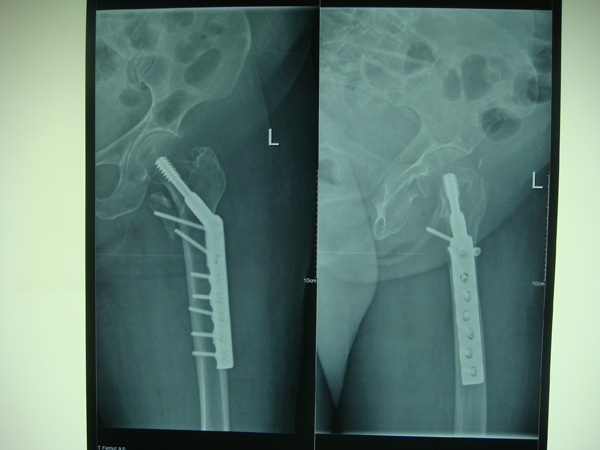

7月9日,莆田盛興醫(yī)院為一名89歲的女性髖部骨折患者順利實(shí)施了手術(shù)。